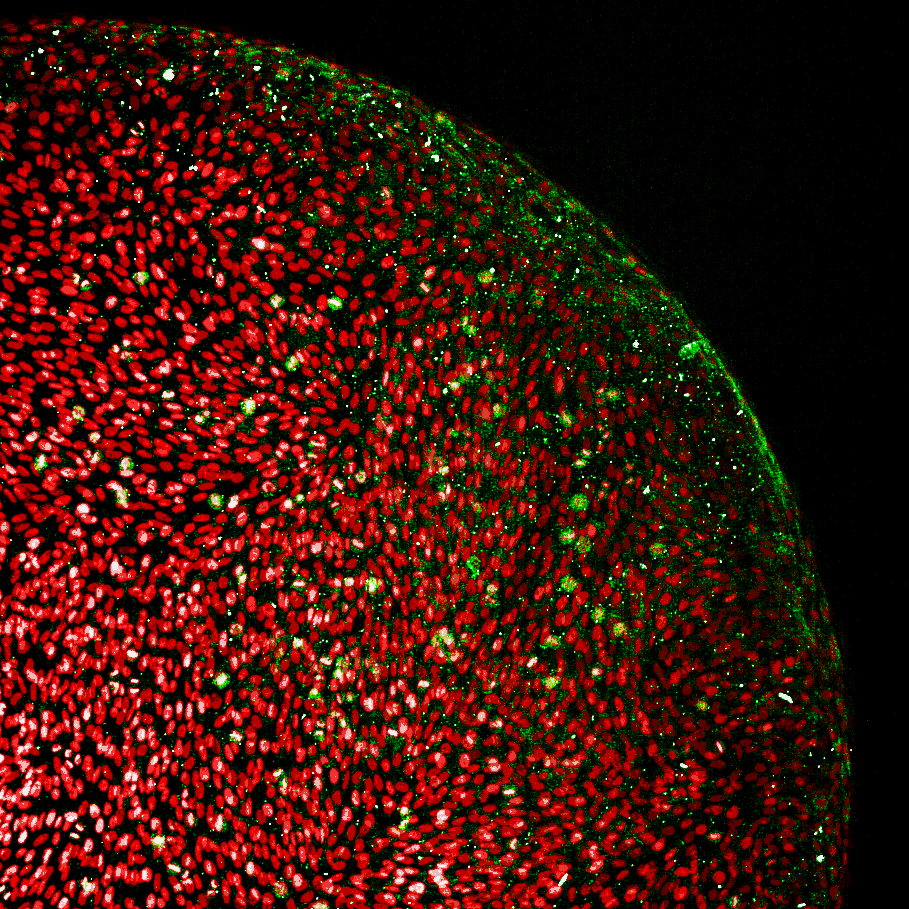

Our 3D patient-derived glioblastoma platform is built on starPEG–glycosaminoglycan hydrogels that recreate brain-like extracellular cues, enabling high-throughput functional drug testing and drug-response profiling in a 384-well format with high-content omics and phenotypic readouts.

Diagram showing a high-throughput screening system for patient-derived 3D glioblastoma models, including primary patient cells, a liquid handling system, 384-well plates with hydrogel components, and an imaging process for quantification and comparison of drug responses with 3D graphics of sample images and analysis results.